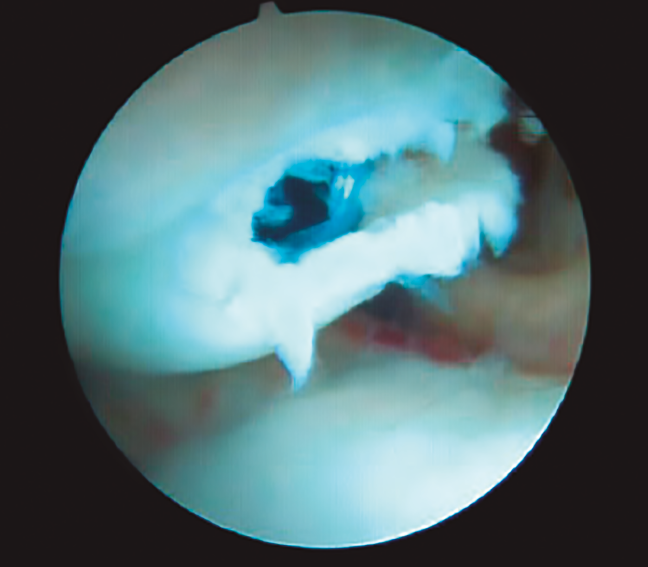

Se comienza la artroscopia en la articulación radiocarpiana a través del portal 3/4 con la colocación de la óptica para realizar un recorrido articular con el fin de identificar la existencia de lesiones asociadas o valorar fracturas del polo proximal del escafoides (Figura 8).

Figura 8. Visualización de la fractura de escafoides desde el portal 6R.